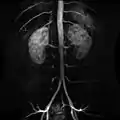

Abdominal aorta

Segments of the aorta, with both suprarenal and infrarenal abdominal aorta

The abdominal aorta and its branches.